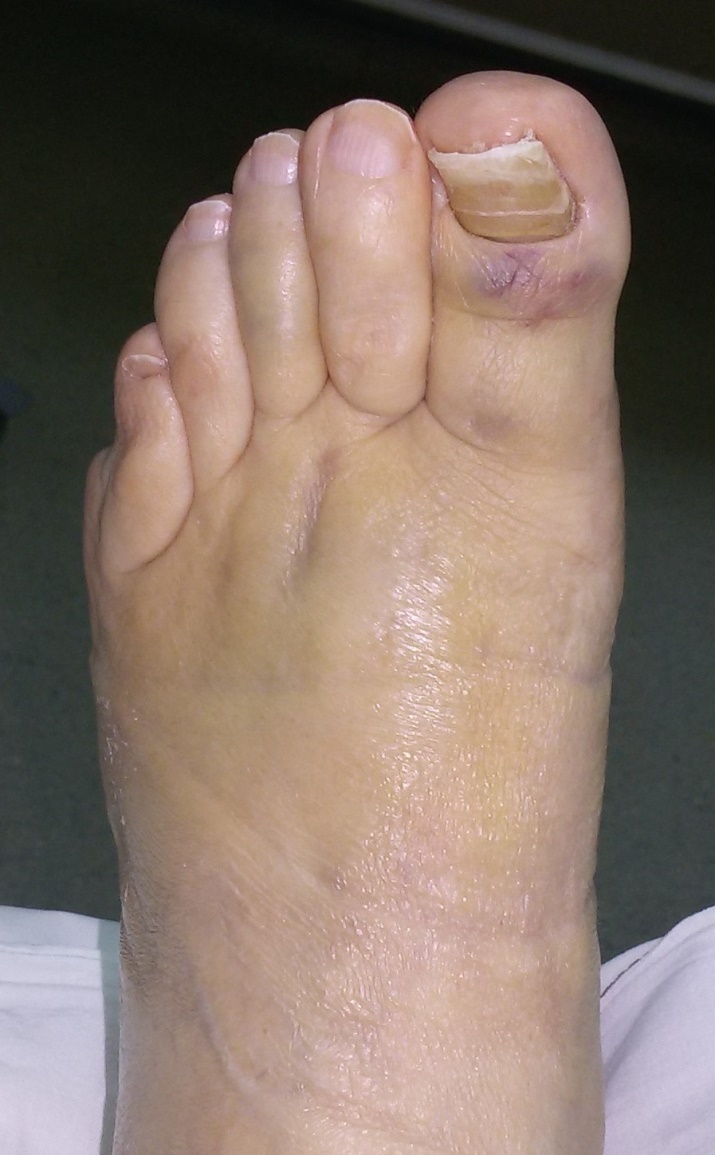

Вот обещанный в чем-то похожий случай. Пациентка 58 лет с тяжелым ревматоидным артритом. Оперировал в 2013 г. В одну сессию сделал чрескожно повторную операцию на стопе (раньше где-то оперировали, пациентка приехала издалека) и малоинвазивный артродез голеностопного сустава (имелась варусная деформация, как компенсация вальгуса колена, на фоне выраженной ревматоидной артропатии). А через неделю – протезирование коленного сустава (фиброзный анкилоз после когда-то выполненной синовэктомии, грубая вальгусная деформация). Понятно, что неделю между операциями стопа торчала в сторону и не была опороспособной. Основное пожелание по коленке было, чтобы сгибалась хоть немного для походов в театр. В конечном счете, сустав сгибался до 90 гр. Фотография стоя была прислана через 2 года после операций. А через 3 года, прошедшим летом, пациентка упала с лестницы: перипротезный перелом бедра. Через 5 дней приехала оперироваться. Отсюда отек на фото стопы. Что интересно, через 2 мес. после остеосинтеза пациентка написала, что только теперь, после перелома, смогла ощутить опору всей поверхностью стопы. До этого пользовалась индивидуальными стельками.